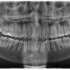

Submitted by kasuma9999 t3_10prqtx in mildlyinteresting

Reply to comment by LordDagron in Xray of my fully horizontal wisdom teeth. by kasuma9999

I xrayed them out 3 years ago and they just begin to murder me since Sunday.